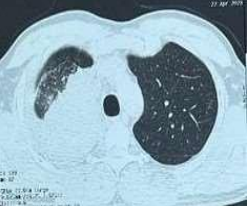

53-year-old male presented to a tertiary care centre elsewhere with complaints of high-grade fever not associated to chills/rigor, productive cough with copious amount of white coloured sputum, breathing difficulty on exertion MMRC Grade III, noisy breathing, chest pain and multiple episodes of haemoptysis. Patient had no other co-morbidities/symptoms of any chronic illness or any other contributary past history. After getting admitted and primary investigations, he was treated with IV antibiotics suspecting pneumonia. After 7 days of treatment patient was referred to our centre as there was no resolution. On clinical examination, patient had shift of trachea to the right side, dullness on percussion, bronchial breath sound and crepitations in the right infraclavicular area. Blood investigations showed leucocytosis (14,000/mm3), elevated levels of ESR (85mm/hr) and CRP (102mg/dl) with no other significant biochemical changes. Chest X-ray taken showed a collapse of the right upper lobe, with the classical ‘Golden S’ sign (figure 1) which raised a suspicion of right upper lobe mass. Further HRCT thorax was taken which showed a ‘bronchial cut off’ sign (figure 2) and an enhancing soft tissue lesion in the right upper lobe with encasement right pulmonary artery and bronchus (figure 3). Patient was taken up for bronchoscopy which showed a right upper lobe mass (figure 4). Bronchial brushings and biopsy (figure 5) were taken and samples were sent for Histopathological study which confirmed Non-Small Cell Carcinoma- Adenocarcinomatous type (figure 6).

Figure 6: Histopathology

Figure 6